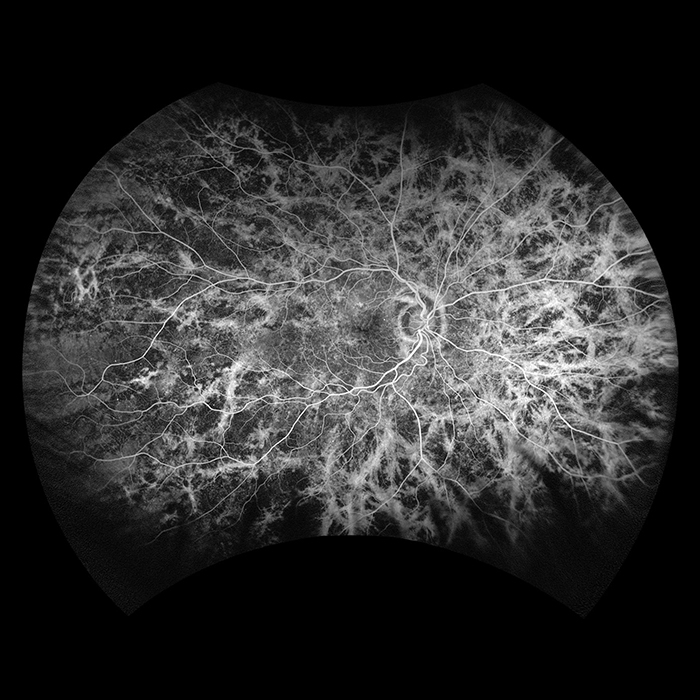

California

California was developed for medical imaging and is a standard for retinal screening programs. California is available in multiple models with multiple imaging modality options. California produces a 200°, single shot retinal image of unrivaled clarity in less than ½ second and is changing the management of diseases including Geographic Atrophy, Diabetic Retinopathy, AMD, and Uveitis.

Why California?

California was developed to facilitate comprehensive eye exams, document findings, and assist eyecare professionals in disease management and treatment. California is available in various device configurations and image modality options for the flexibility to meet the needs and budget of every eyecare practice. Imaging modalities and viewing options are detailed below.

optomap Image Modalities

- color rgb (available with rg,af,fa combined model)

- color rg

- Sensory Retina

- Choroidal

- green af

- blue af

- fa

- icg